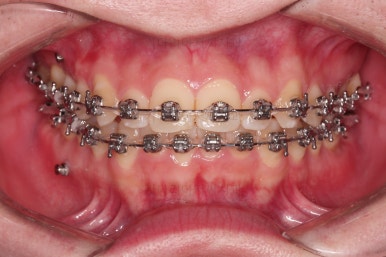

이제 전후 비교를 해볼게요.

1년 7개월 만에 매우 고난이도의 치료를 임플란트 없이 사랑니까지 당겨와서 사용한 만족스러운 치료였습니다.

이상 어금니 결손, 상실치아가 있는 경우 사랑니까지 살려서 앞으로 당겨와서 임플란트 없이 치료를 마루리한 부산교정치과 치료사례였습니다.